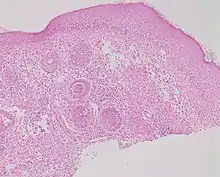

| Secondary syphilis | Various, but often one or a combination of:[21]

|

|

_on_the_soles_of_the_feet._Plantar_lesions-CDC.jpg.webp) |